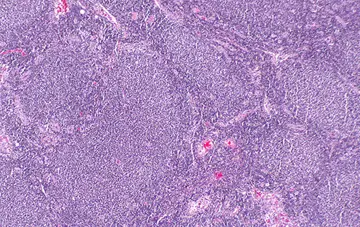

هماتولوژی - صفحه 4